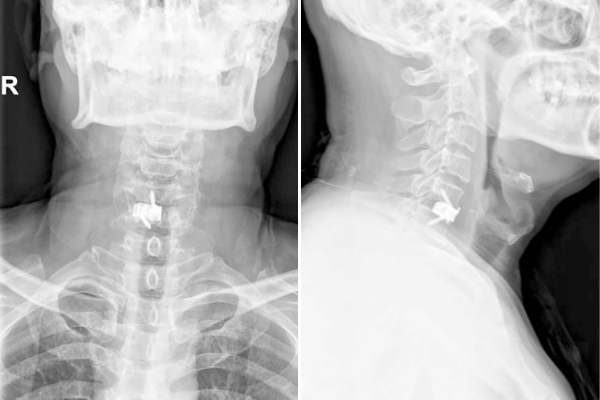

图1 单节段3D打印零切迹融合器置入术后影像

颈椎病是现代人常见的健康问题,长期低头、姿势不良等因素导致颈椎间盘突出、骨质增生,进而压迫神经或脊髓,引发疼痛、麻木甚至肢体无力。传统手术虽能缓解症状,但术后常伴随吞咽不适、异物感等问题。近日,首都医科大学附属北京胸科医院骨科主任贺永雄带领团队成功完成我院首例3D打印零切迹融合器手术(图1),为颈椎病患者提供了更安全、更舒适的解决方案。